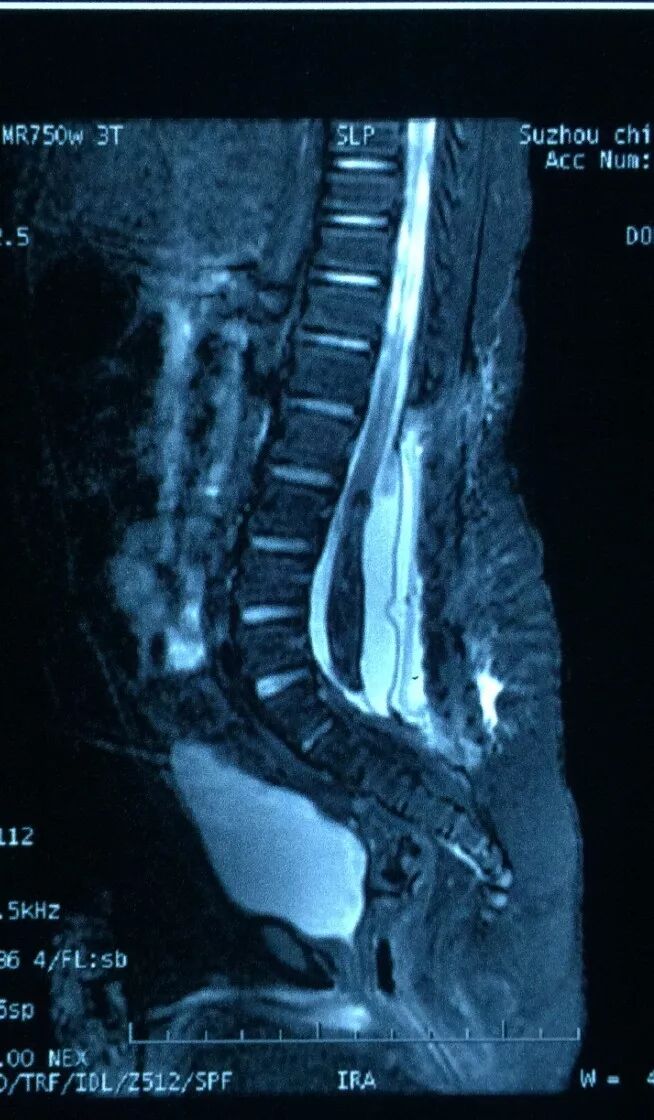

术前影像检查

MR扫描显示骶尾段脊髓脊膜膨出,脑积水,Chiari畸形II型。

术前诊断:骶尾段脊柱裂(脊髓脊膜膨出),Chiari畸形II型,脑积水,双侧神经源性马蹄内翻足。

脊髓栓系发病的原因很多,但其主线是脊髓被缺乏弹性的组织固定并牵拉损伤。脊柱短缩治疗脊髓栓系综合征的的实质是缩短椎管。我们的方法主要是在不需要缩短脊柱的前提下如何缩短椎管。腰椎生理性前屈的主要位置在L4、L5节段。圆椎位置位于L4以下的病人,去掉相应节段的椎板和棘突利于将重建的硬膜囊的后壁取直,“曲线变直线”,事实上缩短了椎管的长度。扩大的椎管有利于脑脊液搏动,避免脊髓神经根被囊壁捕获粘连。术中应该保护好蛛网膜和软脊膜,保持脑脊液清亮,不停地更换蘸水明胶海绵吸收出血,又可以减少脊髓神经根在空气中的暴露。